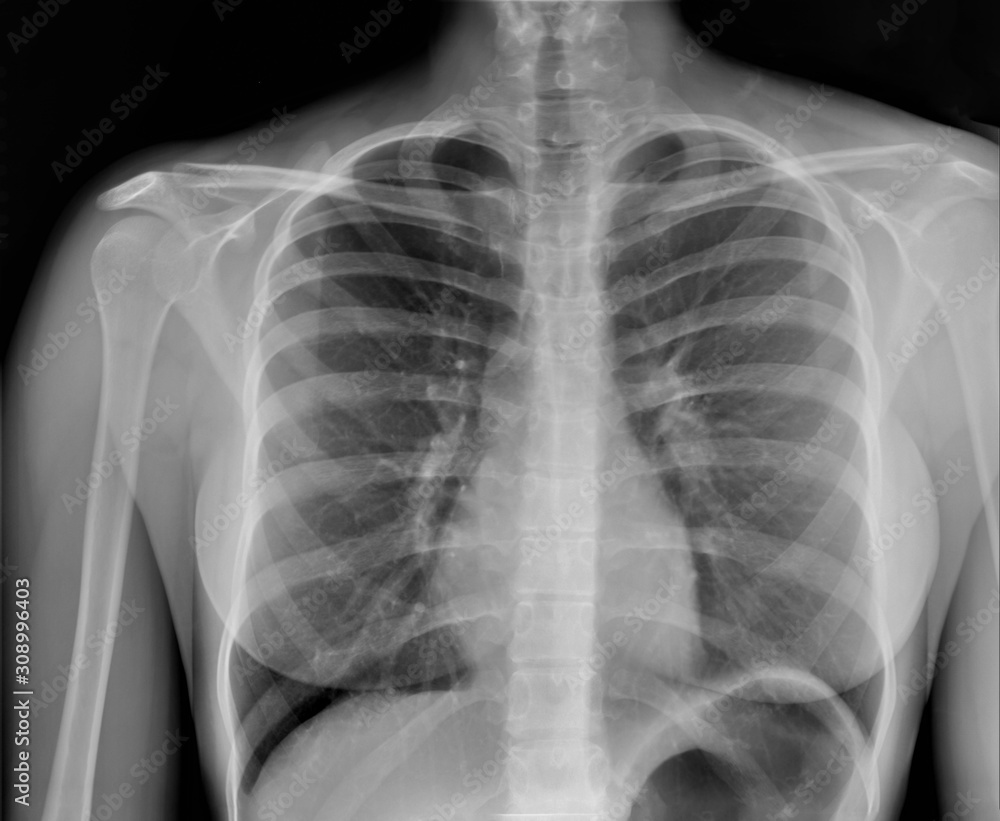

From stock.adobe.com

Pneumonia ( film chest xray show alveolar infiltrate at right middle Chest X Ray Adequate Exposure The interpretation of a chest film. Incomplete inspiration can lead to exaggeration of lung markings and heart size. Cxr is a quick, noninvasive,. Always assess inspiration and lung volumes. The left hemidiaphragm should be visible to the edge of the spine. The space between the medial. In fact every radiologst should be an expert in chest film reading. Left hemidiaphragm. Chest X Ray Adequate Exposure.